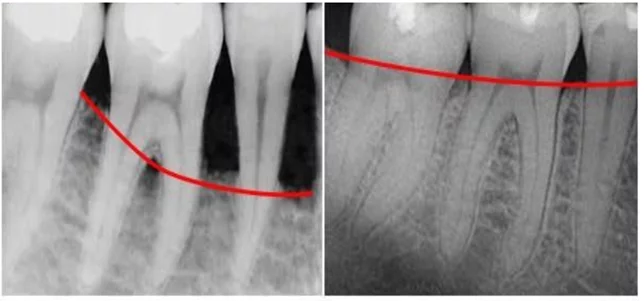

Bạn nên chia sẻ với nha sĩ nếu gặp bất kỳ triệu chứng nào trong số những triệu chứng trên. Tại phòng khám nha khoa, bác sĩ sẽ kiểm tra độ sâu của túi nha chu giữa nướu và răng. Túi nha chu sâu là một triệu chứng ban đầu của bệnh nha chu đang có tiến triển xấu.

Các giai đoạn của bệnh viêm nha chu

Viêm nha chu xuất hiện và tiến triển theo 4 giai đoạn:

- Giai đoạn 1: Vôi răng hình thành do các mảng bám lâu ngày khiến vi khuẩn tích tụ ở cổ răng, kẽ răng gây viêm nướu

- Giai đoạn 2: Viêm nướu gây sưng phù, chảy máu lợi, có giảm giác nhức

- Giai đoạn 3: Viêm nướu trở nặng thành viêm nha chu, hình thành những ổ viêm nhiễm có mủ

- Giai đoạn 4: Viêm nha chu nặng, phá hủy xương răng, gây tụt lợi. Khi đó răng không còn được nướu bao bọc, dễ bị lung lay và người bệnh có nguy cơ rụng răng